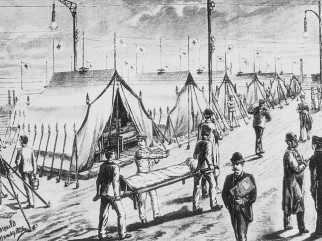

Cholera sickbay in Hamburg Eppendorf in 1892 [7]The balance: